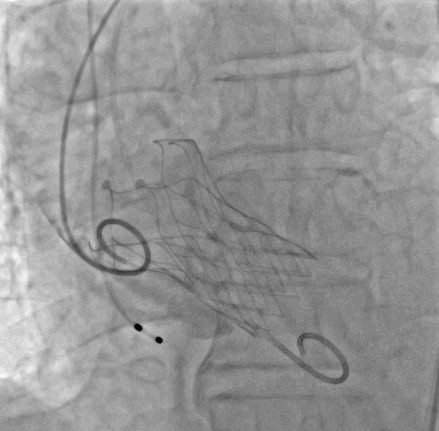

4. 瓣膜植入:输送VitaFlow®TAV27瓣膜跨瓣成功,140次/分起搏,猪尾导管造影定位,释放瓣膜,复查造影提示少许瓣周漏,跨瓣压差4mmHg,更换为猪尾导管后,食道超声提示未见明显瓣周漏,遂撤出导丝导管,缝合右侧股动脉,拔除左侧股动脉鞘管,加压包扎。

释放到1/2处造影

瓣膜完全、释放形态良好